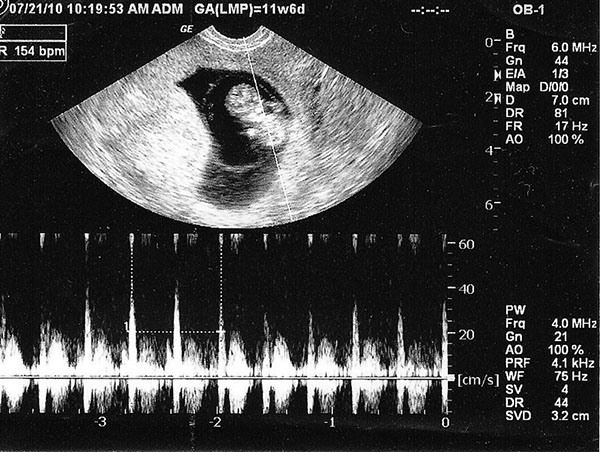

Chắc chắn rằng bất cứ một bà mẹ nào cũng đều mong muốn có thể nghe thấy được tim thai của con mình. Chắc chắn rằng những mẹ lần đầu có em bé thì chắc chắn chưa biết được tuần thứ mấy có tim thai để đi siêu âm nghe tiếng đập của con. Theo bác sĩ Điệp chia sẻ rằng thường phải sau 7 tuần thì mẹ mới có thể nghe được nhịp tim của bé. Nhưng cũng có một vài trường hợp đặc biệt có thể chỉ ở tuần thứ 5 hay thứ 6 mẹ sẽ nghe được tim thai. Và cũng có trường hợp muộn hơn 7 tuần thì mới có thể nghe được.

Về cơ bản thì ở thời điểm tuần thứ 5 hay đầu của tuần thứ 6 nếu siêu âm mẹ có thể sẽ nghe được âm vang của tim. Và để nghe chính xác hơn thì phải qua 7 tuần mới có thể rõ ràng hơn được. Ngoài ra, thời điểm này mẹ khi siêu âm cũng nhìn rõ được phôi thai.